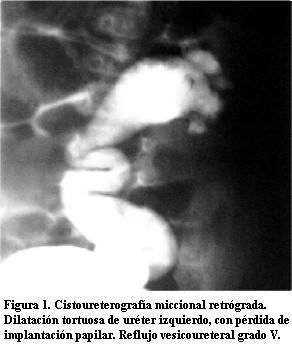

Cistoureterografía miccional retrógrada: RVU grado V a izquierda (figura 1).